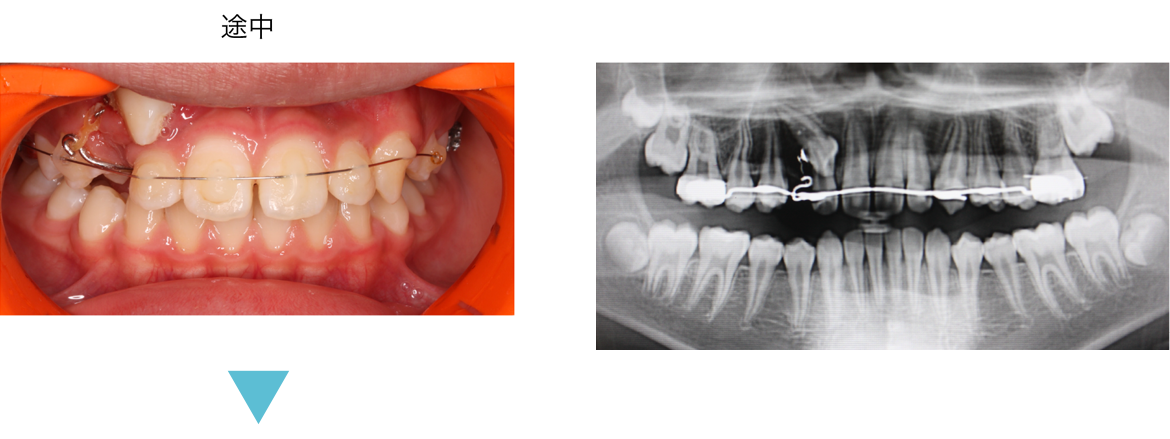

矯正用の拡大装置を使うと顎を広げる作用で歯並びも良くなりますが、鼻腔も広がるので口呼吸を改善し、様々な症状が改善する可能性があります。ぜひご相談ください。

固定式拡大装置は床タイプと違って自分で外せないので、確実に治療が進みます。 また床タイプでの拡大では傾斜移動になり根尖が動きませんが、固定式の場合は歯体移動ができ、鼻腔も広がる可能性があり口呼吸から鼻呼吸への改善可能性があります。